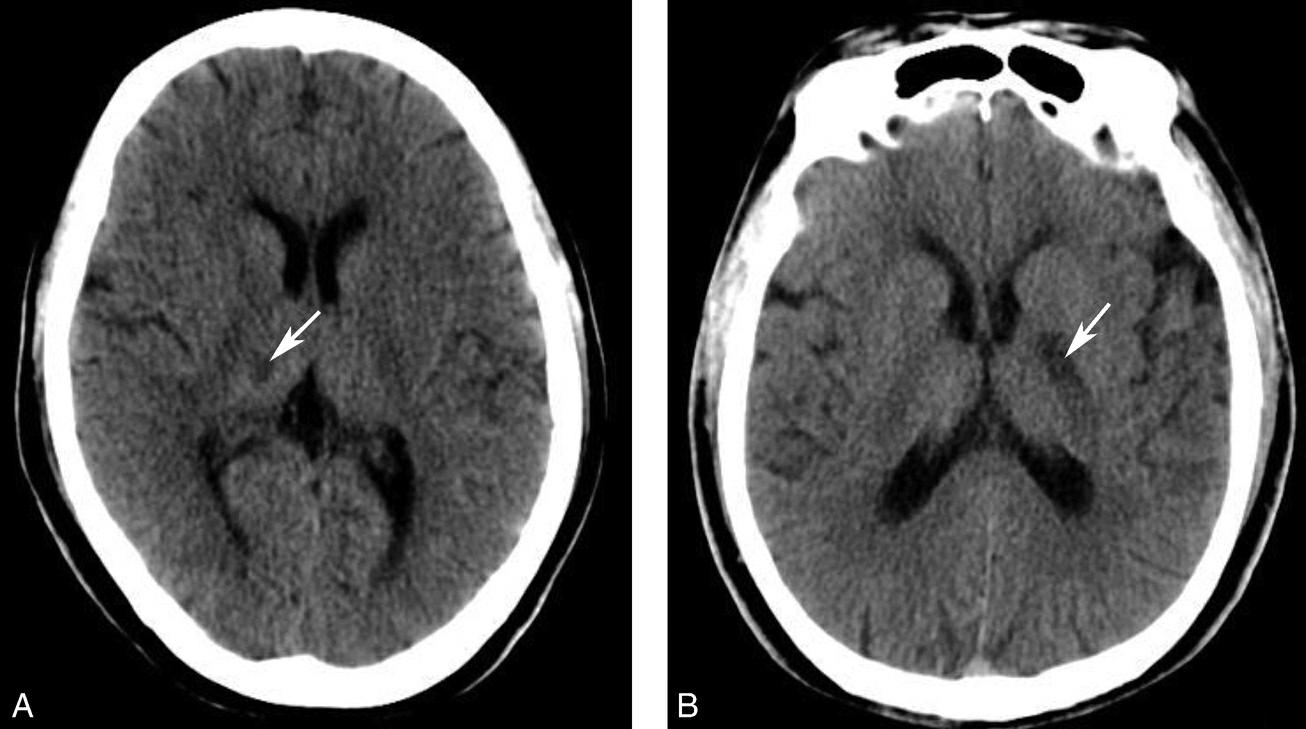

蝶鞍两侧为海绵窦,其内包含颈内动脉及第Ⅲ~Ⅵ对脑神经。海绵窦的密度升高或体积增大常提示病变存在。海绵窦外侧为颞叶,两者之间隔以海绵窦外侧壁。鞍背后方为桥前池及其后方的脑桥,桥前池内可见基底动脉断面,呈圆形稍高密度影。层面中部两侧为颞骨乳突部,其内气化的骨性腔隙为乳突气房。脑桥后方为第四脑室,呈半圆形或新月形,小脑半球的病变(如肿瘤、炎症、出血等)常压迫第四脑室,导致其变形甚至闭塞(图1-2-13)。两侧小脑半球间为小脑蚓部。小脑半球与颞骨乳突部间可见乙状窦。小脑蚓部后方为直窦与上矢状窦汇入窦汇处,窦汇两侧为横窦。静脉窦血栓时可见上述静脉窦增宽、密度明显升高(图1-2-14)。

图1-2-13 第四脑室变形(小脑转移瘤)

A.第四脑室受压变形右移(白箭),提示左侧小脑半球病变;B.左侧小脑半球环形强化结节(黑箭),为瘤体,其周围伴有低密度水肿区